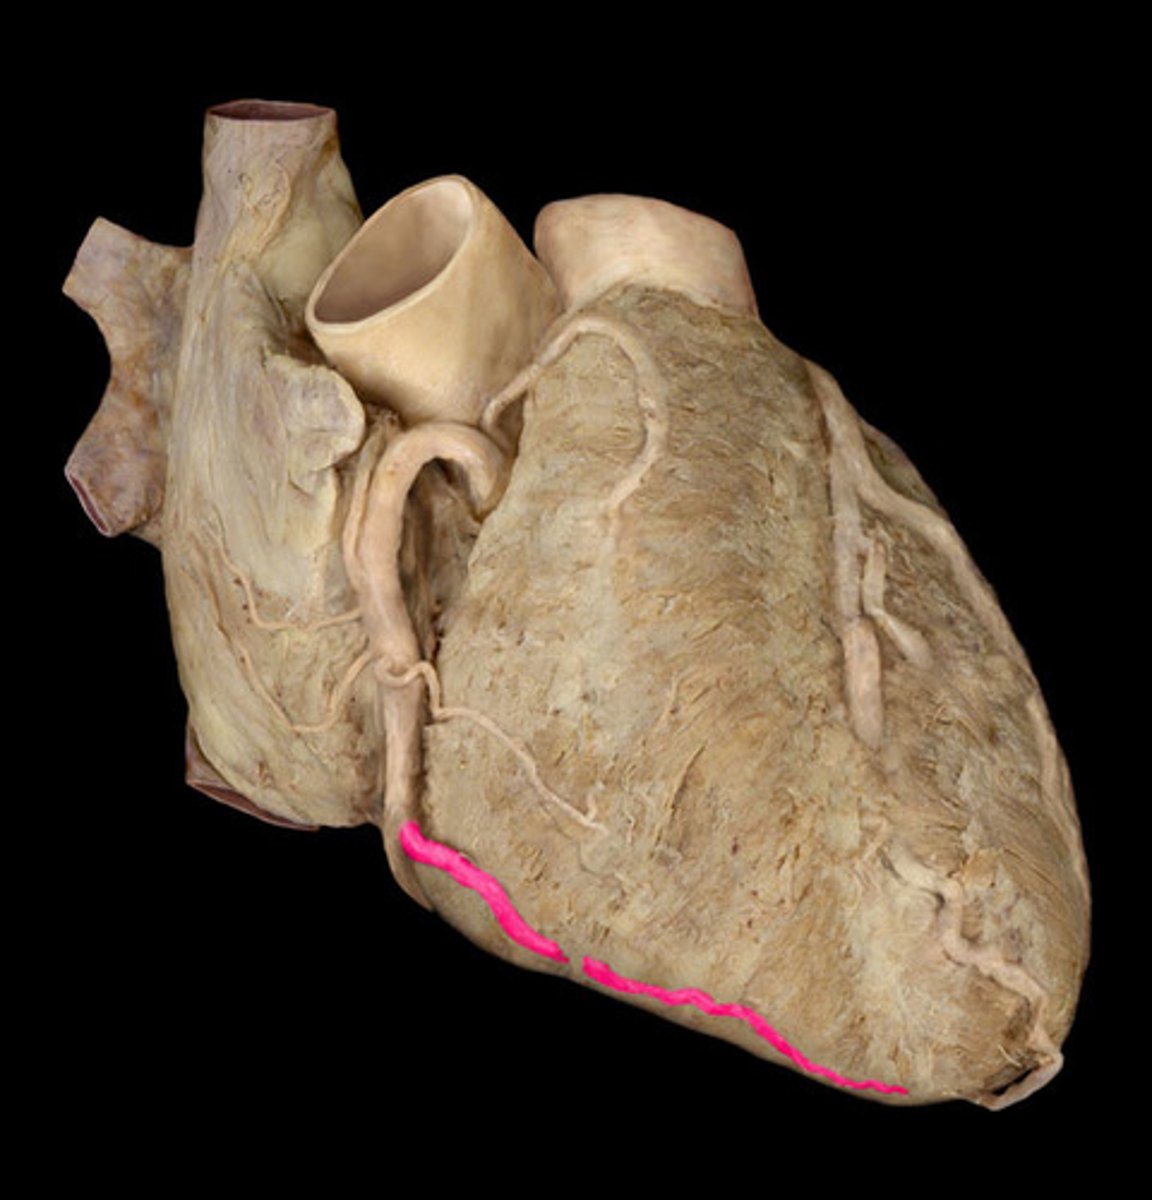

anterior interventricular artery or left anterior descending artery (of left coronary artery)

#4

left marginal artery

#3